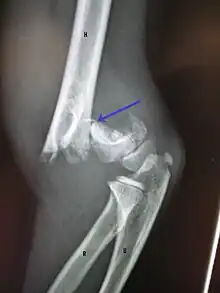

Midshaft humerus fracture with callus formation

Definitive diagnosis of humerus fractures is typically made through radiographic imaging. For proximal fractures, X-rays can be taken from a scapular anteroposterior (AP) view, which takes an image of the front of the shoulder region from an angle, a scapular Y view, which takes an image of the back of the shoulder region from an angle, and an axillar lateral view, which has the patient lie on his or her back, lift the bottom half of the arm up to the side, and have an image taken of the axilla region underneath the shoulder.[9] Fractures of the humerus shaft are usually correctly identified with radiographic images taken from the AP and lateral viewpoints.[12] Damage to the radial nerve from a shaft fracture can be identified by an inability to bend the hand backwards or by decreased sensation in the back of the hand.[5] Images of the distal region are often of poor quality due to the patient being unable to extend the elbow because of pain. If a severe distal fracture is suspected, then a computed tomography (CT) scan can provide greater detail of the fracture. Nondisplaced distal fractures may not be directly visible; they may only be visible due to fat being displaced because of internal bleeding in the elbow.[7]

Fractures of the humerus are classified based on the location of the fracture and then by the type of fracture. There are three locations that humerus fractures occur: at the proximal location, which is the top of the humerus near the shoulder, in the middle, which is at the shaft of the humerus, and the distal location, which is the bottom of the humerus near the elbow.[9] Proximal fractures are classified into one of four types of fractures based on the displacement of the greater tubercle, the lesser tubercle, the surgical neck, and the anatomical neck, which are the four parts of the proximal humerus, with fracture displacement being defined as at least one centimeter of separation or an angulation greater than 45 degrees. One-part fractures involve no displacement of any parts of the humerus, two-part fractures have one part displaced relative to the other three; three-part fractures have two displaced fragments, and four-part fractures have all fragments displaced from each other.[13][14][3] Fractures of the humerus shaft are subdivided into transverse fractures, spiral fractures, "butterfly" fractures, which are a combination of transverse and spiral fractures, and pathological fractures, which are fractures caused by medical conditions.[12] Distal fractures are split between supracondylar fractures, which are transverse fractures above the two condyles at the bottom of the humerus, and intercondylar fractures, which involve a T- or Y-shaped fracture that splits the condyles.[7]